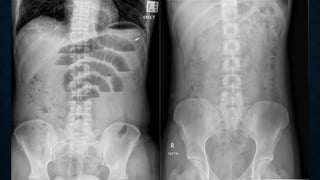

This document provides an overview of x-rays for medical students, covering topics such as ensuring x-rays are well-aligned, exposure levels, common artifacts and anatomical features, abdominal x-ray positions and views, and specialized x-rays including barium swallows, enemas, and tests to examine the esophagus, small bowel, biliary tree, and kidneys.